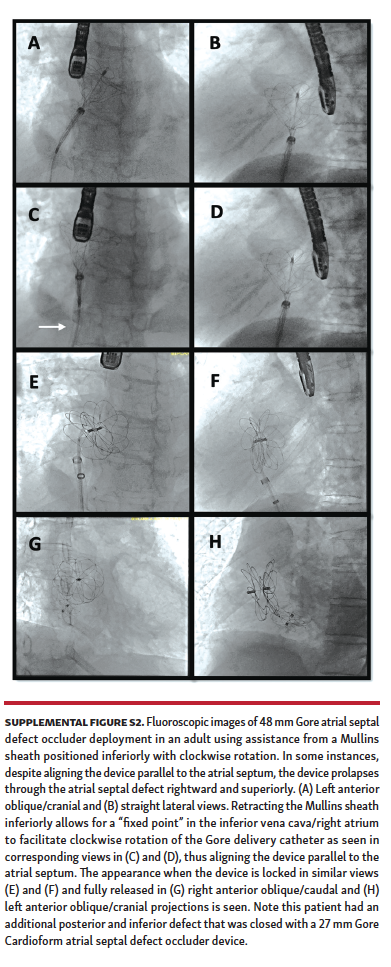

A total of 98 patients underwent attempted ASD closure during the study period (70 patients from the Gore ASSURED Clinical Study-Pivotal and Continued Access studies) and 28 patients after the study period. Of these patients, 52 underwent attempted secundum ASD closure using a long Mullins sheath (Supplemental Figures S1 and S2), while 46 patients underwent attempted secundum ASD closure with the Gore Cardioform delivery catheter through a short sheath in standard fashion.

Mullins-sheath facilitated Gore Cardioform ASD occluder delivery technique. The mechanism of favorable exaggeration of the angle of the Gore Cardioform ASD occluder delivery system when used with a Mullins sheath is seen in Figure 1. In large defects or in defects with deficient rims, the angulation of the Gore delivery catheter may not allow for alignment of the device parallel to the atrial septum, with resultant device prolapse superiorly through the defect into the right atrium (Figure 2). In such situations, the short sheath was exchanged for an appropriately sized 63 cm-long or 75 cm-long Mullins sheath in the left atrium and the dilator and wire were removed (same Fr size as required short sheath Fr size). When used in combination with a Mullins sheath, the angulation is exaggerated enough to facilitate better alignment parallel to the atrial septum (Figure 3). The Mullins sheath was rotated clockwise to assume a posterior orientation to align the device parallel to the atrial septum as it was being delivered. The Gore Cardioform ASD occluder delivery catheter was then advanced through the Mullins sheath, which was positioned with continuous clockwise rotation, often by the assistant, as the primary operator deployed the device. In some cases, despite this maneuver, the device was not aligned parallel to the atrial septum. In such cases, once the left atrial side of the device was deployed and aligned in the best possible way, the Mullins sheath was withdrawn (if 63 cm-long sheath was used) to the inferior vena cava or right atrium to serve as a “fixed point,” whereby further clockwise rotation of the Gore delivery catheter could be performed if needed to facilitate further device alignment as parallel to the atrial septum as possible (Figure 4). In some cases, the Gore delivery catheter was rotated 180° clockwise despite the use of the Mullins sheath to facilitate capture of the aortic and superior vena cava rims. Use of the Mullins sheath also facilitated delivery of the device when inferior disc prolapse into the left atrium was encountered (Figure 5). Finally, in some cases, the tip of the Gore Cardioform ASD occluder delivery catheter was also hand-shaped to further exaggerate its angle. The use of the Mullins sheath was at the discretion of the implanting physician.